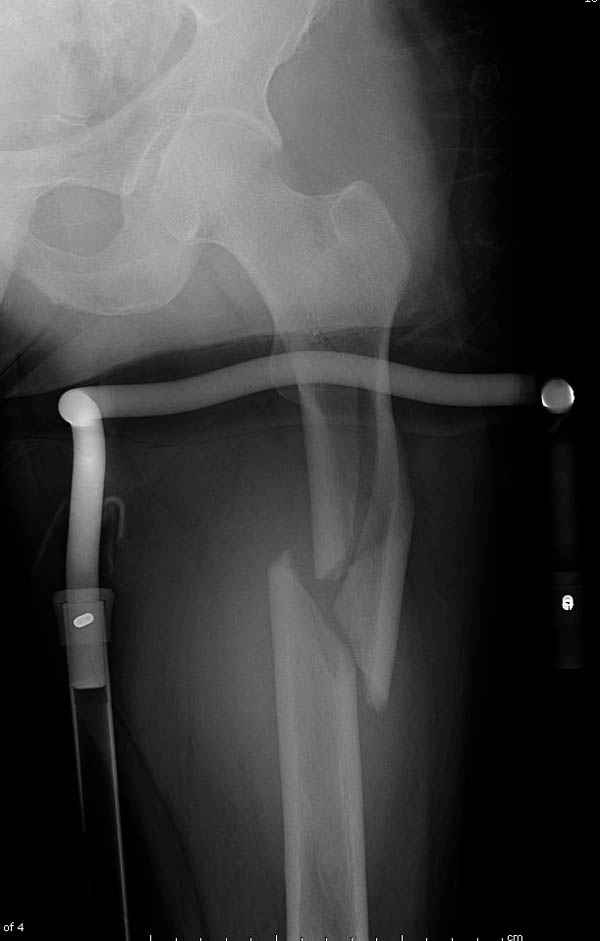

Среди русскоговорящих коллег Ортофорум стал одним из мест, где многие из нас черпают знания для решения своих ежедневных проблем в виде практических советов и обмена опытом. Кроме таких советов, Ортофорум стал источником новых познаний среди ортопедов, особенно по редко встречающимся состояниям в ортопедии. Продолжая традицию, я хотел бы представить редко встречающий случай перелома бедра у больного с гемофилией. Больному 42, гемофилия типа А, из истории упал с высоты около 1,5 метра, переправлен из другой больницы. По происхождению мексиканец, 10 лет назад по поводу артроза пр. коленного сустава в Мексике сделано протезирование, которое закончилось ампутацией выше коленного сустава. При поступлении бедро напряженное, сосудистых и неврологических расстройств нет. На рентгенограмме оскольчатый перелом бедра с вовлечением проксимальной спирали в шейку бедра. Хотели бы знать тактику ведения подобных больных и на что надо обратить внимание? Djoldas Kuldjanov, MD Department of Orthopedic Surgery St. Louis University Medical Center

Учитывая, что случай ургентный, больной поступил вечером, не стали делать вытяжение и срочно провели операцию по фиксации перелома бедра антеградным штифтом Versa Nail от DePuy.

Для профилактики дальнейшего раскола в шейке предварительно во время проксимального рассверливания спереди и сзади провели временные спицы, которые в дальнейшем были заменены на шурупы (miss nail method)